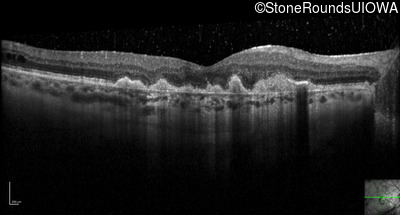

Optical Coherence Tomography - Right - 20/80 -1

Exemplar / OCT Stack